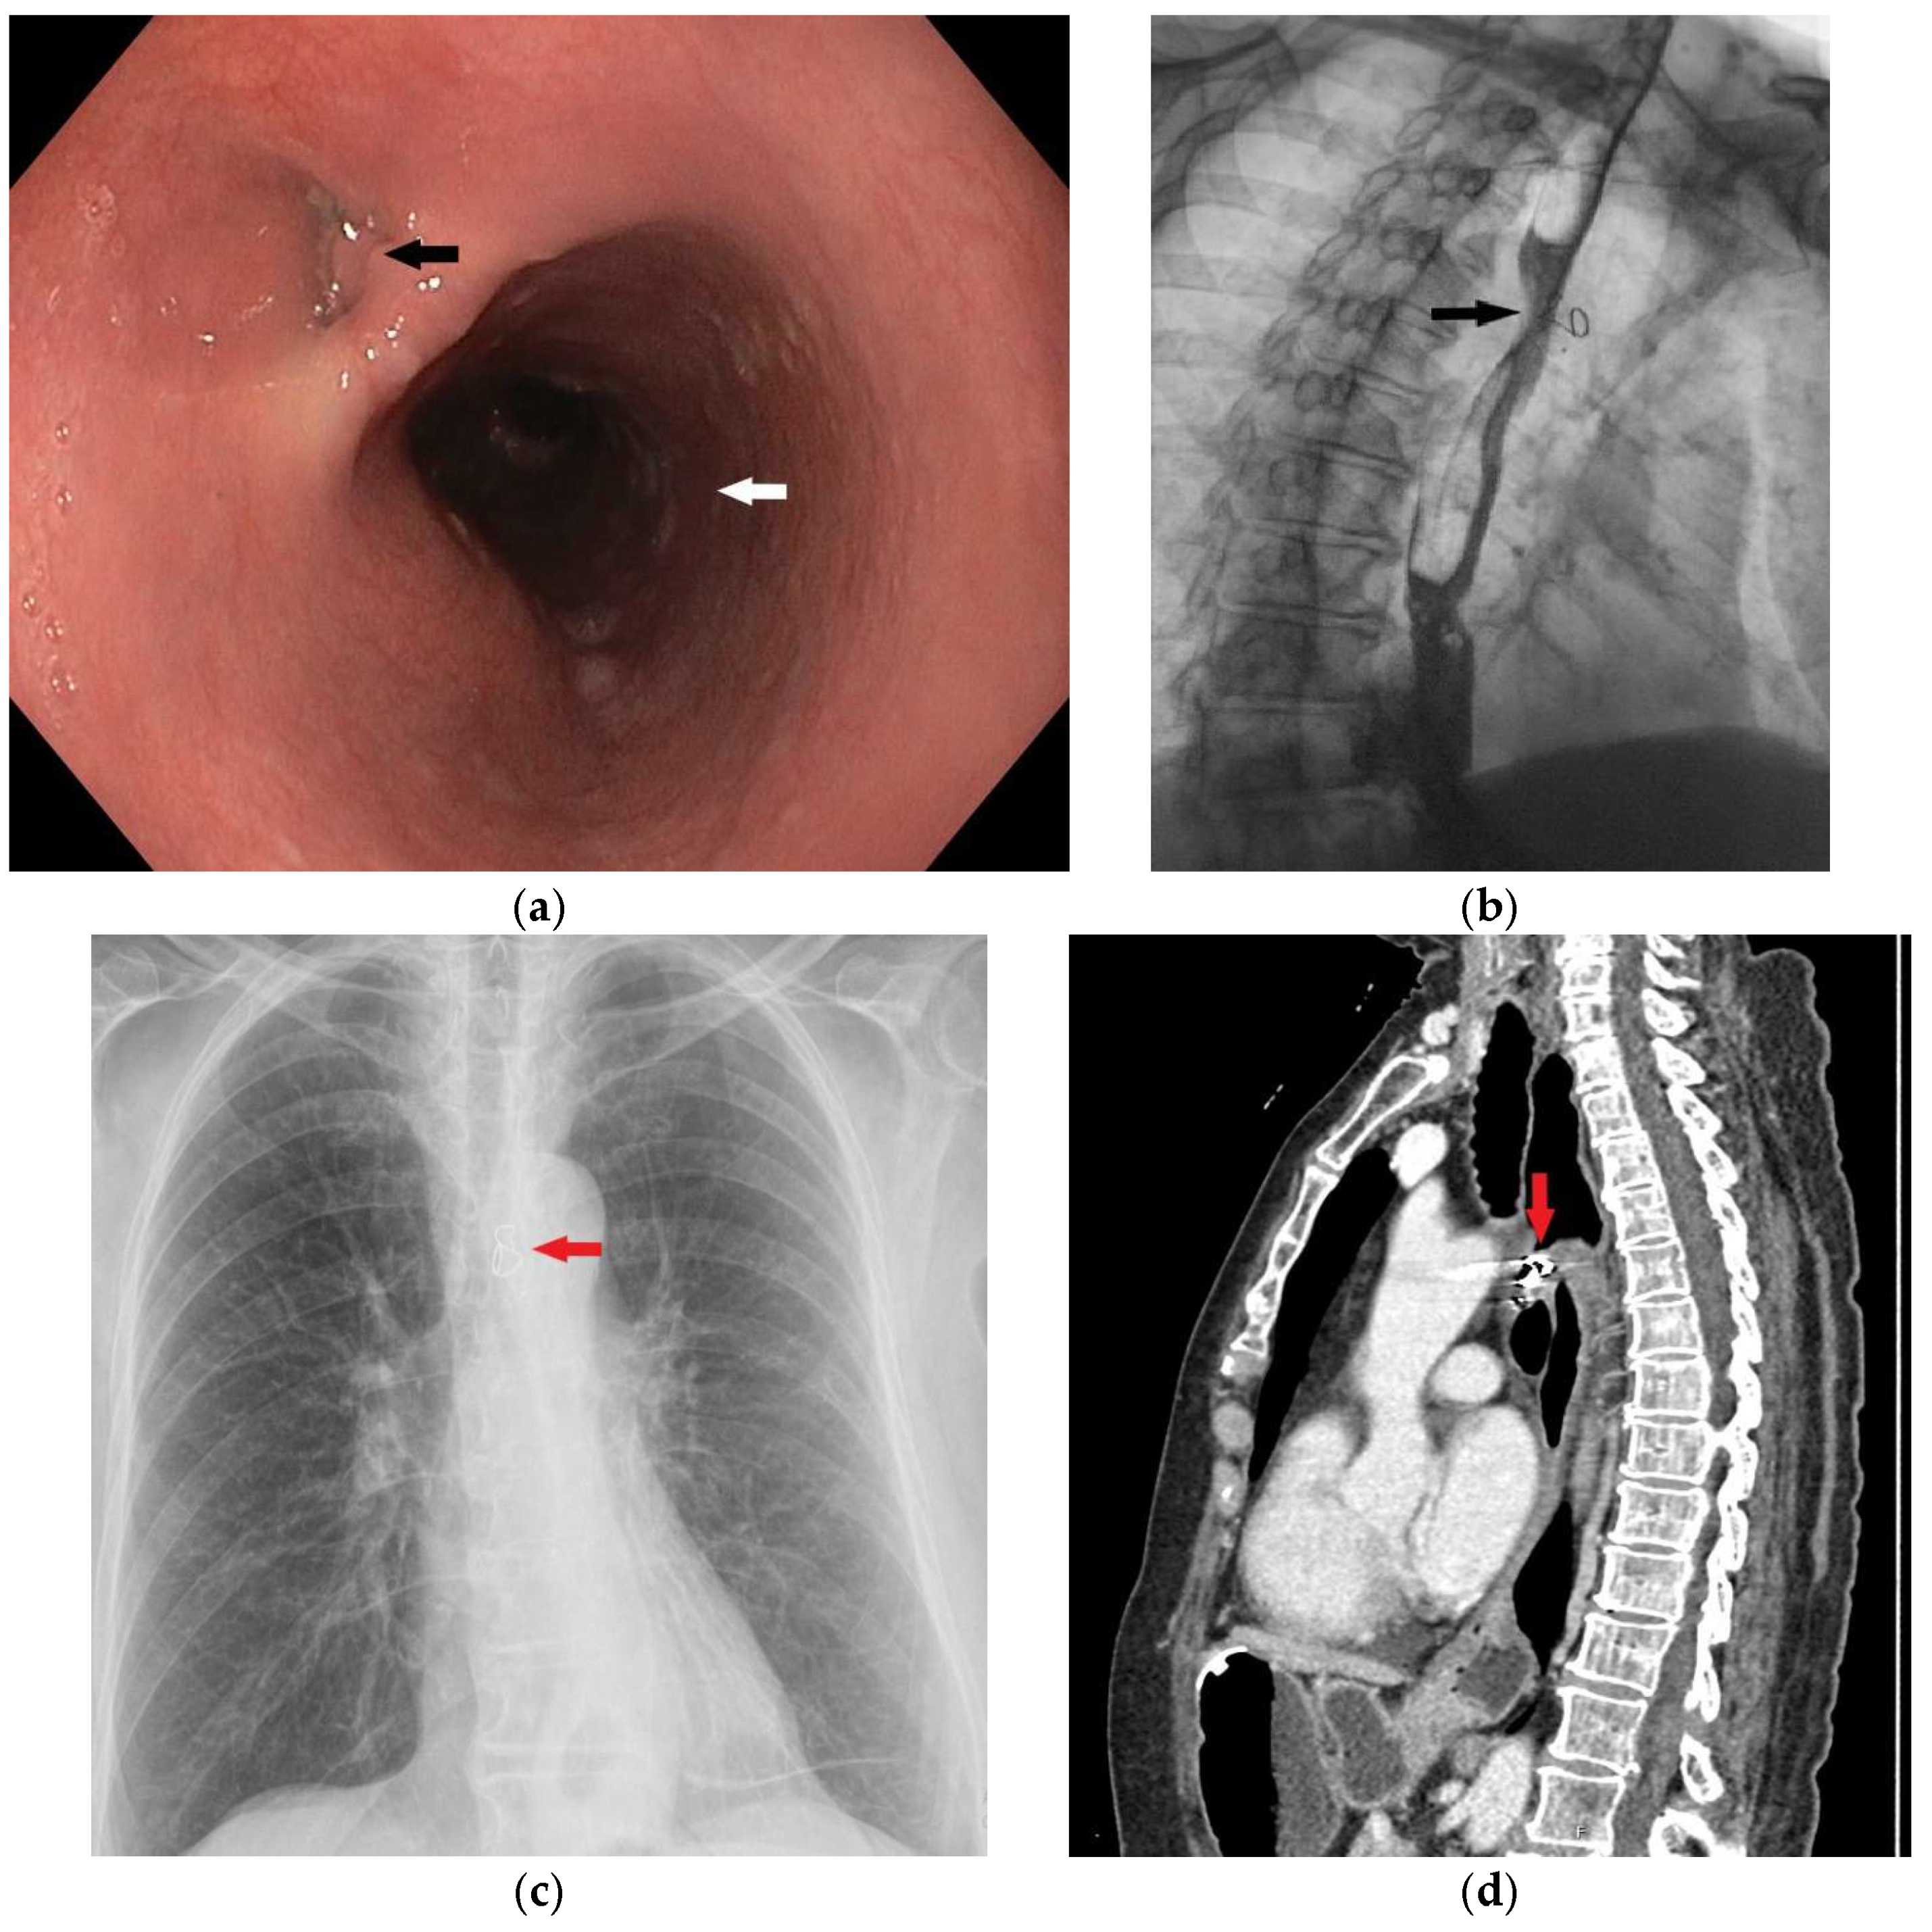

Figure 1. Upper gastrointestinal endoscopy in a female patient, 60 years old, revealed the presence of a fistula opening 20 cm from the incisors. This image shows the opening of the fistulous canal (black arrow) and the lumen of the esophagus (white arrow). The patient was admitted to the regional hospital for laparoscopic cholecystectomy. The prior day, ERCP procedure was performed, and a gallstone was removed from the main hepatic duct. Immediately after the initiation of the surgical procedure, and creation of the pneumoperitoneum, the patient experienced dramatic respiratory instability, a drop in oxygen saturation, and extreme gastric air dilatation, so the surgical procedure was abandoned. Liquid green output, highly suspicious for gastric content, was observed from the endotracheal tube. An emergency CT was performed, confirming the diagnosis of tracheoesophageal fistula. Two days later, the patient was admitted to the Intensive Care Department of the Clinic for Digestive Surgery, University Clinical Center of Serbia. The patient was intubated, sedated, and on continuous vasopressor stimulation. Tracheoesophageal fistula (TEF) in adults is usually an acquired condition, which can be further divided into benign and malignant TEF. Benign fistulas are mostly iatrogenic (post-intubation, post-surgery, post-radiation) [1]. Post-intubation trauma is responsible for approximately 75% of benign tracheoesophageal fistula cases [2]. The diagnostic modalities include contrast radiography, CT imaging, bronchoscopy, and upper gastrointestinal endoscopy. Upper GI endoscopy clearly shows a defect in the esophageal wall with a formed fistulous tract which was confirmed by a CT scan showing a pathological communication between the anterior wall of the esophagus and the initial part of the left bronchus. The fistulous tract has a maximum lumen width of about 6 mm (Figure 2). MDCT revealed esophago-tracheal fistula, with the ostium on the esophagus 11 mm of width, 6 mm opening on the tracheal wall, and fistulous tractus 6 mm in diameter.

Figure 4. Contrast radiography is a very useful method in terms of establishing this diagnosis. The appearance of contrast in the lumen of the tracheobronchial tree (black arrow) is a direct sign of the fistulization of these structures within the esophagus. This image shows a clear esophagobronchial leak (fistula), which initiated a pronounced cough during the patient’s examination. Tracheobronchoscopy was also performed, showing an opening on the left side of tracheal bifurcation. In the further course of treatment, percutaneous endoscopic gastrostomy (PEG) was performed, and feeding via PEG was initiated. The patient responded well to antibiotics treatment, and was extubated 7 days after the admission to the intensive care unit. Surgery usually represents the primary treatment modality for acquired TEF. However, when surgery is contraindicated or cannot be performed as a primary solution, non-surgical treatment options may be explored. These can serve as a bridge to definitive surgical repair or, in cases of smaller fistulas, may even offer a definitive therapeutic option [3]. Esophageal stenting is an attractive, minimally invasive approach, used in treating predominantly malignant TEFs but also benign etiology [4]. Studies show a great decrease in respiratory complications, length of hospital stay, and overall quality of life, as well as better performance rate in these patients [5,6]. A retrospective study, comparing 22 patients with benign TEF treated with esophageal stenting showed successful closure of the fistula, obtained in 45% of cases. However, if the fistula is located in the proximal third of the esophagus, stenting may not be feasible [7]. Other authors utilize esophageal stenting together with airway stenting. This kind of approach may be more effective than esophageal stenting alone; however, the friction between the two stents can often damage the tissue between the trachea and esophagus. As a result, this combined approach is reserved only in selected cases [8]. After stabilizing the patient’s general condition and conducting a detailed case analysis, experts in this field decided to use a minimally invasive treatment option provided by interventional vascular radiology and attempt to close the fistulous tract by placing an IMPEDE Embolization plug coil to seal the opening in the wall of the esophagus and the trachea. In consultation with the interventional radiologist, the procedure was precisely planned. First, a flexible endoscope was introduced into the esophagus and a guidewire was placed from the lumen of the esophagus into the fistulous tract and a bronchoscope was used to confirm that the end of the guidewire was in the lumen of the trachea. Then, two IMPEDE Embolization plugs were successively placed one on top of the other, to fill the fistulous canal.

Figure 6. A metal coil (IMPEDE Embolization plug) was placed into the fistula tract (red arrow) by an interventional radiologist. The white arrow shows the lumen of the esophagus (a). The correct localization of the placed coil was confirmed by a chest x-ray (blact arrow) (b).

Figure 8. In order to thoroughly control and monitor the unusual procedure, all necessary diagnostic methods were performed three months after and the correct position and clear epithelialization of the fistulous tract were confirmed, first by upper GI endoscopy (a) (black arrow showing the obliterated lumen of the opening in the esophageal wall) and then by contrast X-ray examination (b), where no extraluminal gastrografin enema was observed (black arrow). An upright posteroanterior (PA) chest radiograph (c) shows the bent wire component of the coil in a correct position (red arrow), while a CT examination (d) confirms the correct localization of the coil within the fistulous tract with completely closed openings in the wall of the esophagus and trachea (red arrow). At that time, percutaneous gastrostomy was removed, and three months after a planned laparoscopic cholecystectomy was performed without intraoperative or postoperative complications. In the recent literature, off-label occluding devices have been used in treating TEF, usually cardiac septal defect occluders. These kinds of devices have been utilized in selected cases, especially in benign TEF and broncho-esophageal fistula [10]. However, its use has been associated with great airway complications, such as airway obstruction mainly due to mucus build up and granulation tissue. In some cases, a denovo fistula could arise due to the erosive effect that the device could have on the tissue [11]. Other approaches have used an Acell matrix (a decellularized porcine urinary bladder matrix), which has been used in treatment of benign TEFs due to its ability to enhance the healing process. Complete closure has been reported in some cases within 10 days [12]. Nevertheless, these approaches remain rarely used due to limited evidence and lack of validation in larger patient groups. Tissue adhesives such as fibrin and cyanoacrylate glue have represented another modality that can be utilized alone or in addition to other occluding devices [13]. The application of these adhesive glues is usually reserved for the pediatric population but has been found in the treatment of the adult population [14]. These agents show a better success in treating more proximal lesions, where the applicability of stents is limited. Having said that, greater outcomes using these agents are usually seen in smaller fistulae and could offer a safer approach in patients with contraindication for severe surgical procedures [15,16]. Endoluminal vacuum-assisted closure (EVAC) therapy has recently emerged as a potential option for TEF management. While promising, EVAC use in TEF remains largely limited to case reports and small series [17].